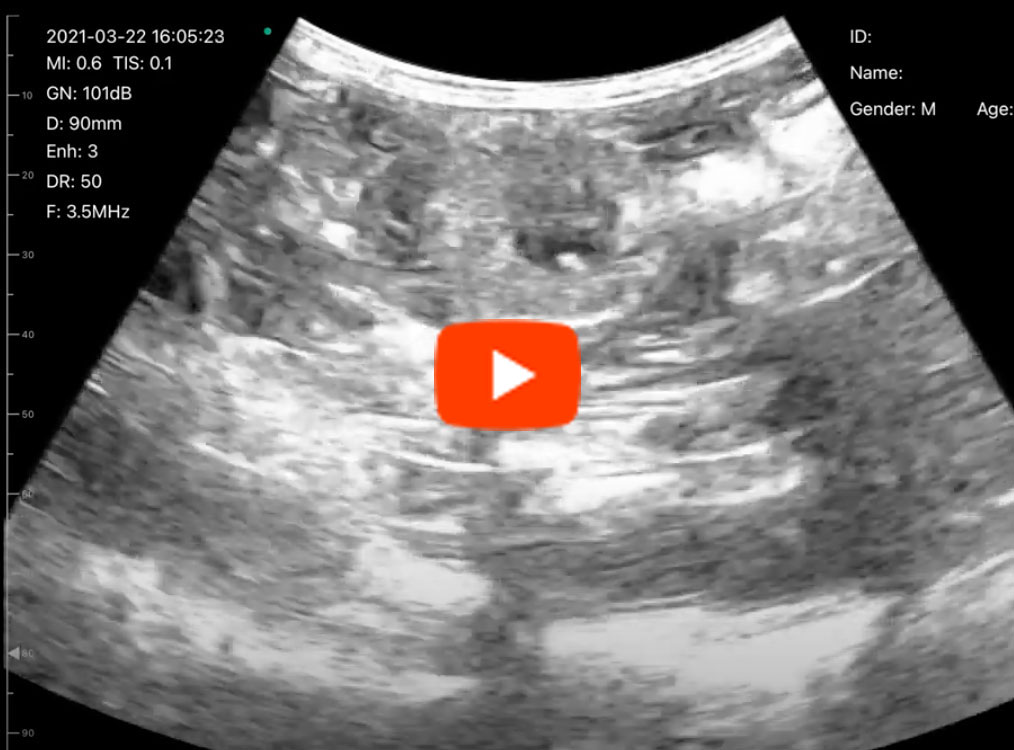

C6C動画1

C6C動画2

C6C動画3

C6C動画4